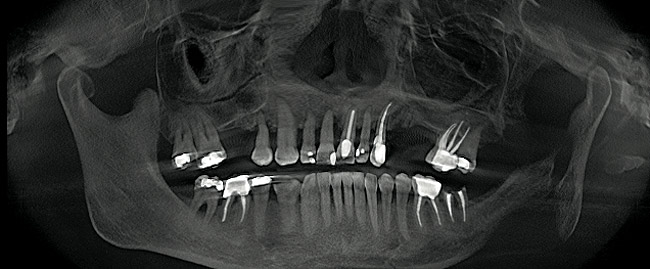

Figure 1  Note wide flap reflection necessary for titanium mesh removal and implant placement. The apical extent of the flap is necessary not only to remove the mesh but also two fixation screws that need to be placed at a safe distance from the apices of the adjacent teeth.

Figure 1

Figure 13  Pretreatment panorex demonstrating hopeless condition of maxillary dentition as well as mandibular molar teeth.

Figure 13